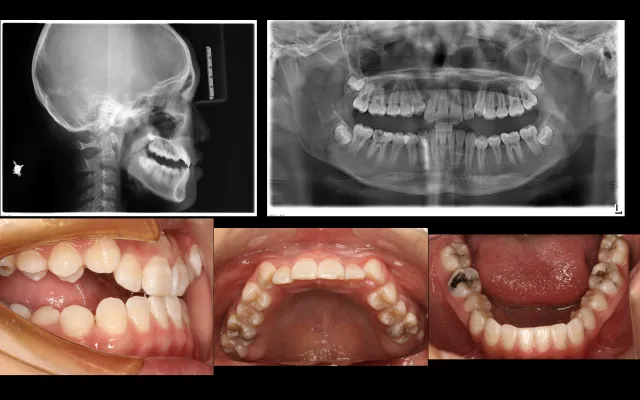

反颌病例的矫治策略(升级版)

1.反颌形成原因

2.不同时期反颌的治疗理念及治疗方法

3.如何高效解决反颌

4. 10个典型反颌案例分析

5.牙性反颌、功能性反颌、骨性反颌的诊断及鉴别诊断

6.牙性反颌功能性反颌的矫治策略及解析

课程重点:

骨性反颌的矫治策略、骨性反颌➕开颌的矫治策略、

骨性反颌➕中重度拥挤的矫治策略、

骨性反颌正畸掩饰治疗的托槽转矩选择、

骨性反颌的拔牙病例解析